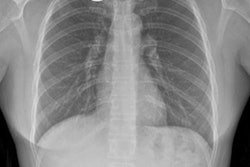

The company has received orders in China for 10 mobile BodyTom scanners, it said. CT is becoming increasingly recognized as the best imaging modality to diagnose COVID-19, according to the firm.